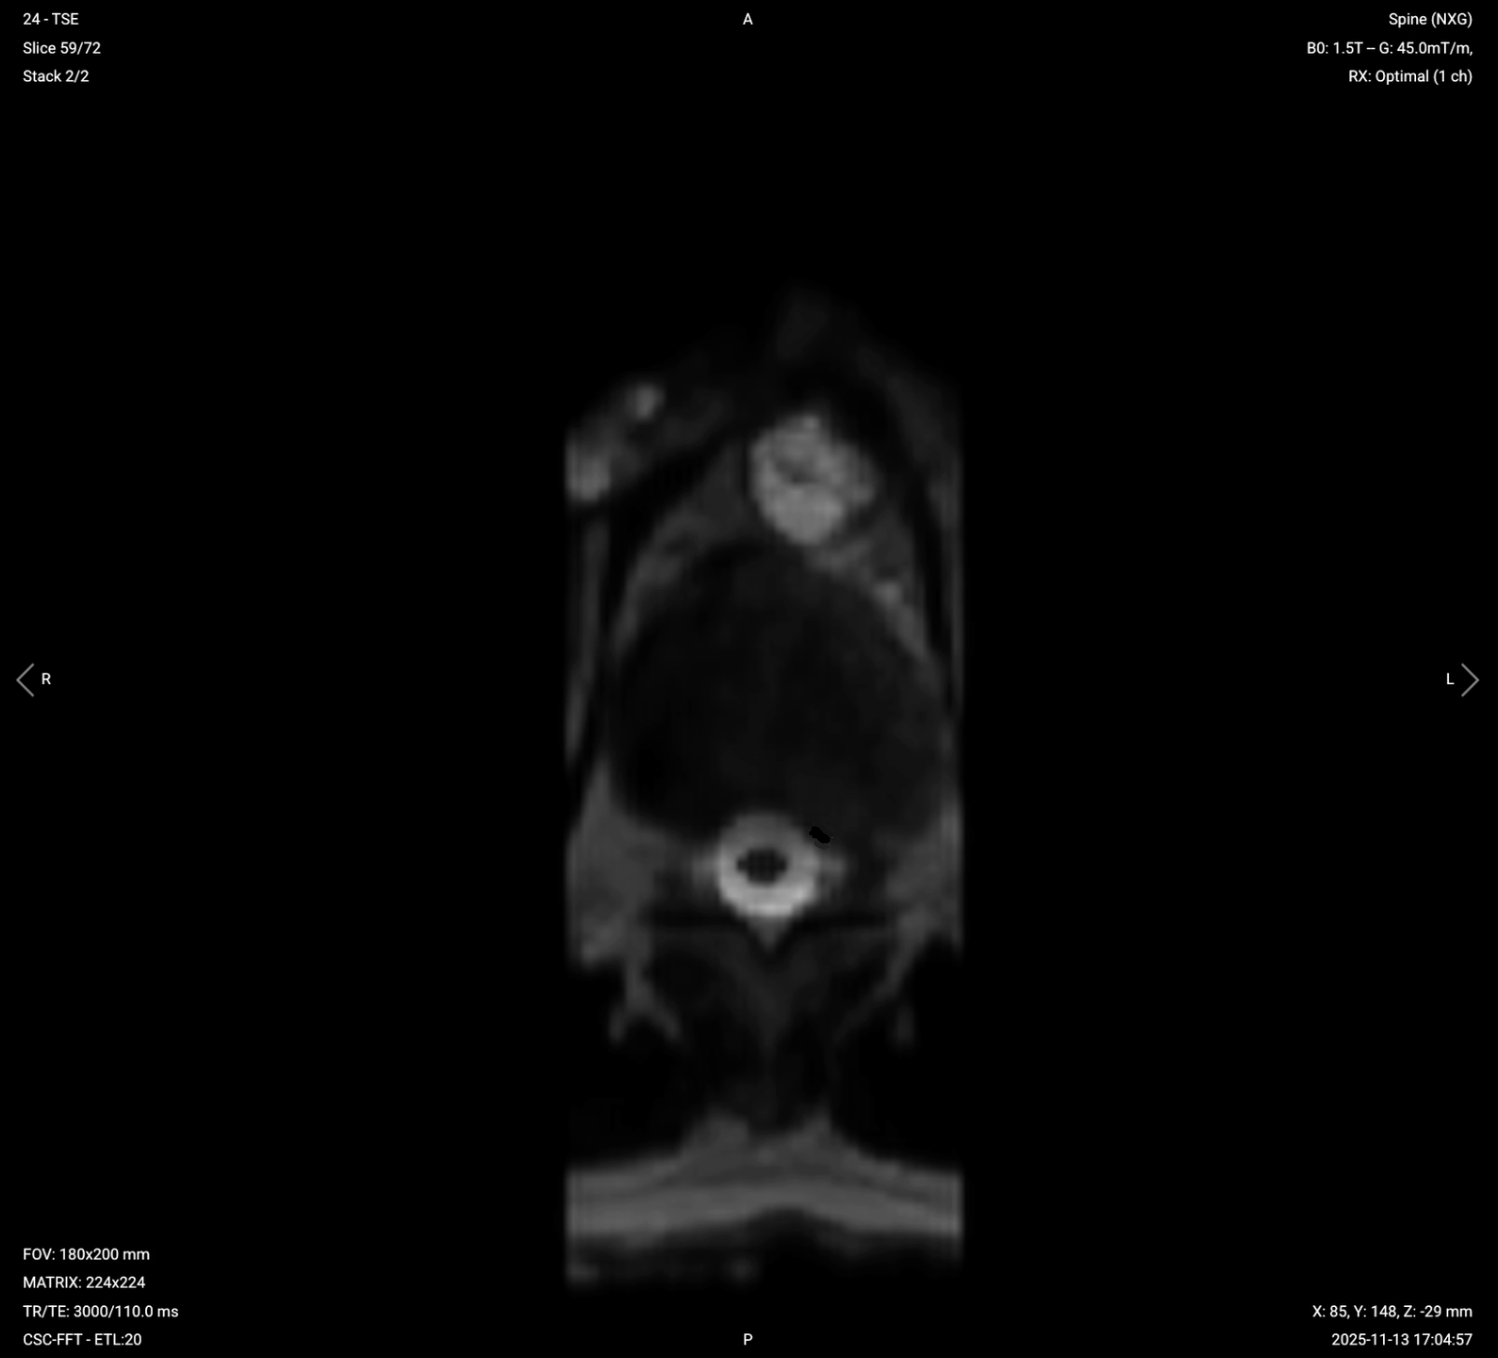

Parameters for Axial T2 TSE:

| Field-of-View (FOV) | 180 × 200 mm | Small FOV focused on the thoracic spine region, minimizing unnecessary coverage to reduce scan time and optimize resolution. |

| Matrix | 224 × 224 | Medium matrix size provides good resolution with faster acquisition, balancing detail with scan time and SNR. |

| Foldover Direction (Phase) | Anterior-to-Posterior (AP) | Avoids motion artifacts from cardiac and respiratory movement. |

| Number of Slices | 50-70 (single stack) 30–40 per stack (double stack) |

Enough slices to cover all 12 thoracic vertebrae. |

| Slice Thickness | 4 mm | Medium thickness provides good anatomical detail without increasing scan time excessively. |

| Slice Gap | 0.4 mm | 10% of slice thickness prevents crosstalk while ensuring continuity. |

| NEX / Averages | 1–2 | Provides adequate SNR while controlling scan time. |

| Turbo Factor / ETL | 16–24 | Higher turbo factor enhances T2 contrast and reduces scan time. |

| Bandwidth | 50,000 Hz | Medium bandwidth balances SNR with chemical shift artifact reduction. Lower than typical values to improve SNR in the challenging thoracic region. |

| Fold-over Suppression | Yes | Prevents wrap-around artifacts. |

✅ Axial T2 TSE of Thoracic Spine – Correct Image Example:

Things to Look for in Axial T2: